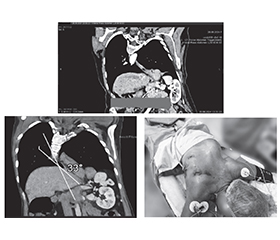

Клінічний випадок: мініінвазивна езофагектомія за McKeown у пацієнтки зі сколіозом ІІІ ступеня

Рак стравоходу — онкологічне захворювання, яке характеризується високою летальністю та часто пізньою діагностикою. Основними гістологічними формами є плоскоклітинний рак та аденокарцинома. Клінічно хворі можуть скаржитися на прогресуючу дисфагію, втрату маси тіла, біль за грудниною або в спині, охриплість голосу. Діагностика включає ендоскопію з біопсією, КТ, ПЕТ-КТ для оцінки стадії пухлини. Лікування залежить від стадії: комбінована терапія (хіміотерапія, променева терапія + хірургія) є стандартом при локалізованому раку. Хірургічне втручання — езофагектомія — залишається основним методом лікування, особливо у пацієнтів без віддалених метастазів. Мініінвазивна езофагектомія за McKeown — це комбінований хірургічний підхід до видалення стравоходу при злоякісному новоутворенні, що поєднує лапароскопічний етап із торакоскопічним доступом, а також цервікальний етап. Переваги включають зменшення післяопераційного болю, менш тривале перебування в стаціонарі, швидше відновлення та зниження частоти ускладнень. Але наявність тяжких супутніх патологій, як-от сколіоз III ступеня, значно ускладнює оперативне втручання та потребує ретельного анестезіологічного та хірургічного планування. За умов мультидисциплінарного підходу — з урахуванням анестезіологічного забезпечення, адаптації етапів операції до анатомічних змін та продуманого післяопераційного ведення — можливо досягти позитивного результату навіть у складних клінічних ситуаціях.